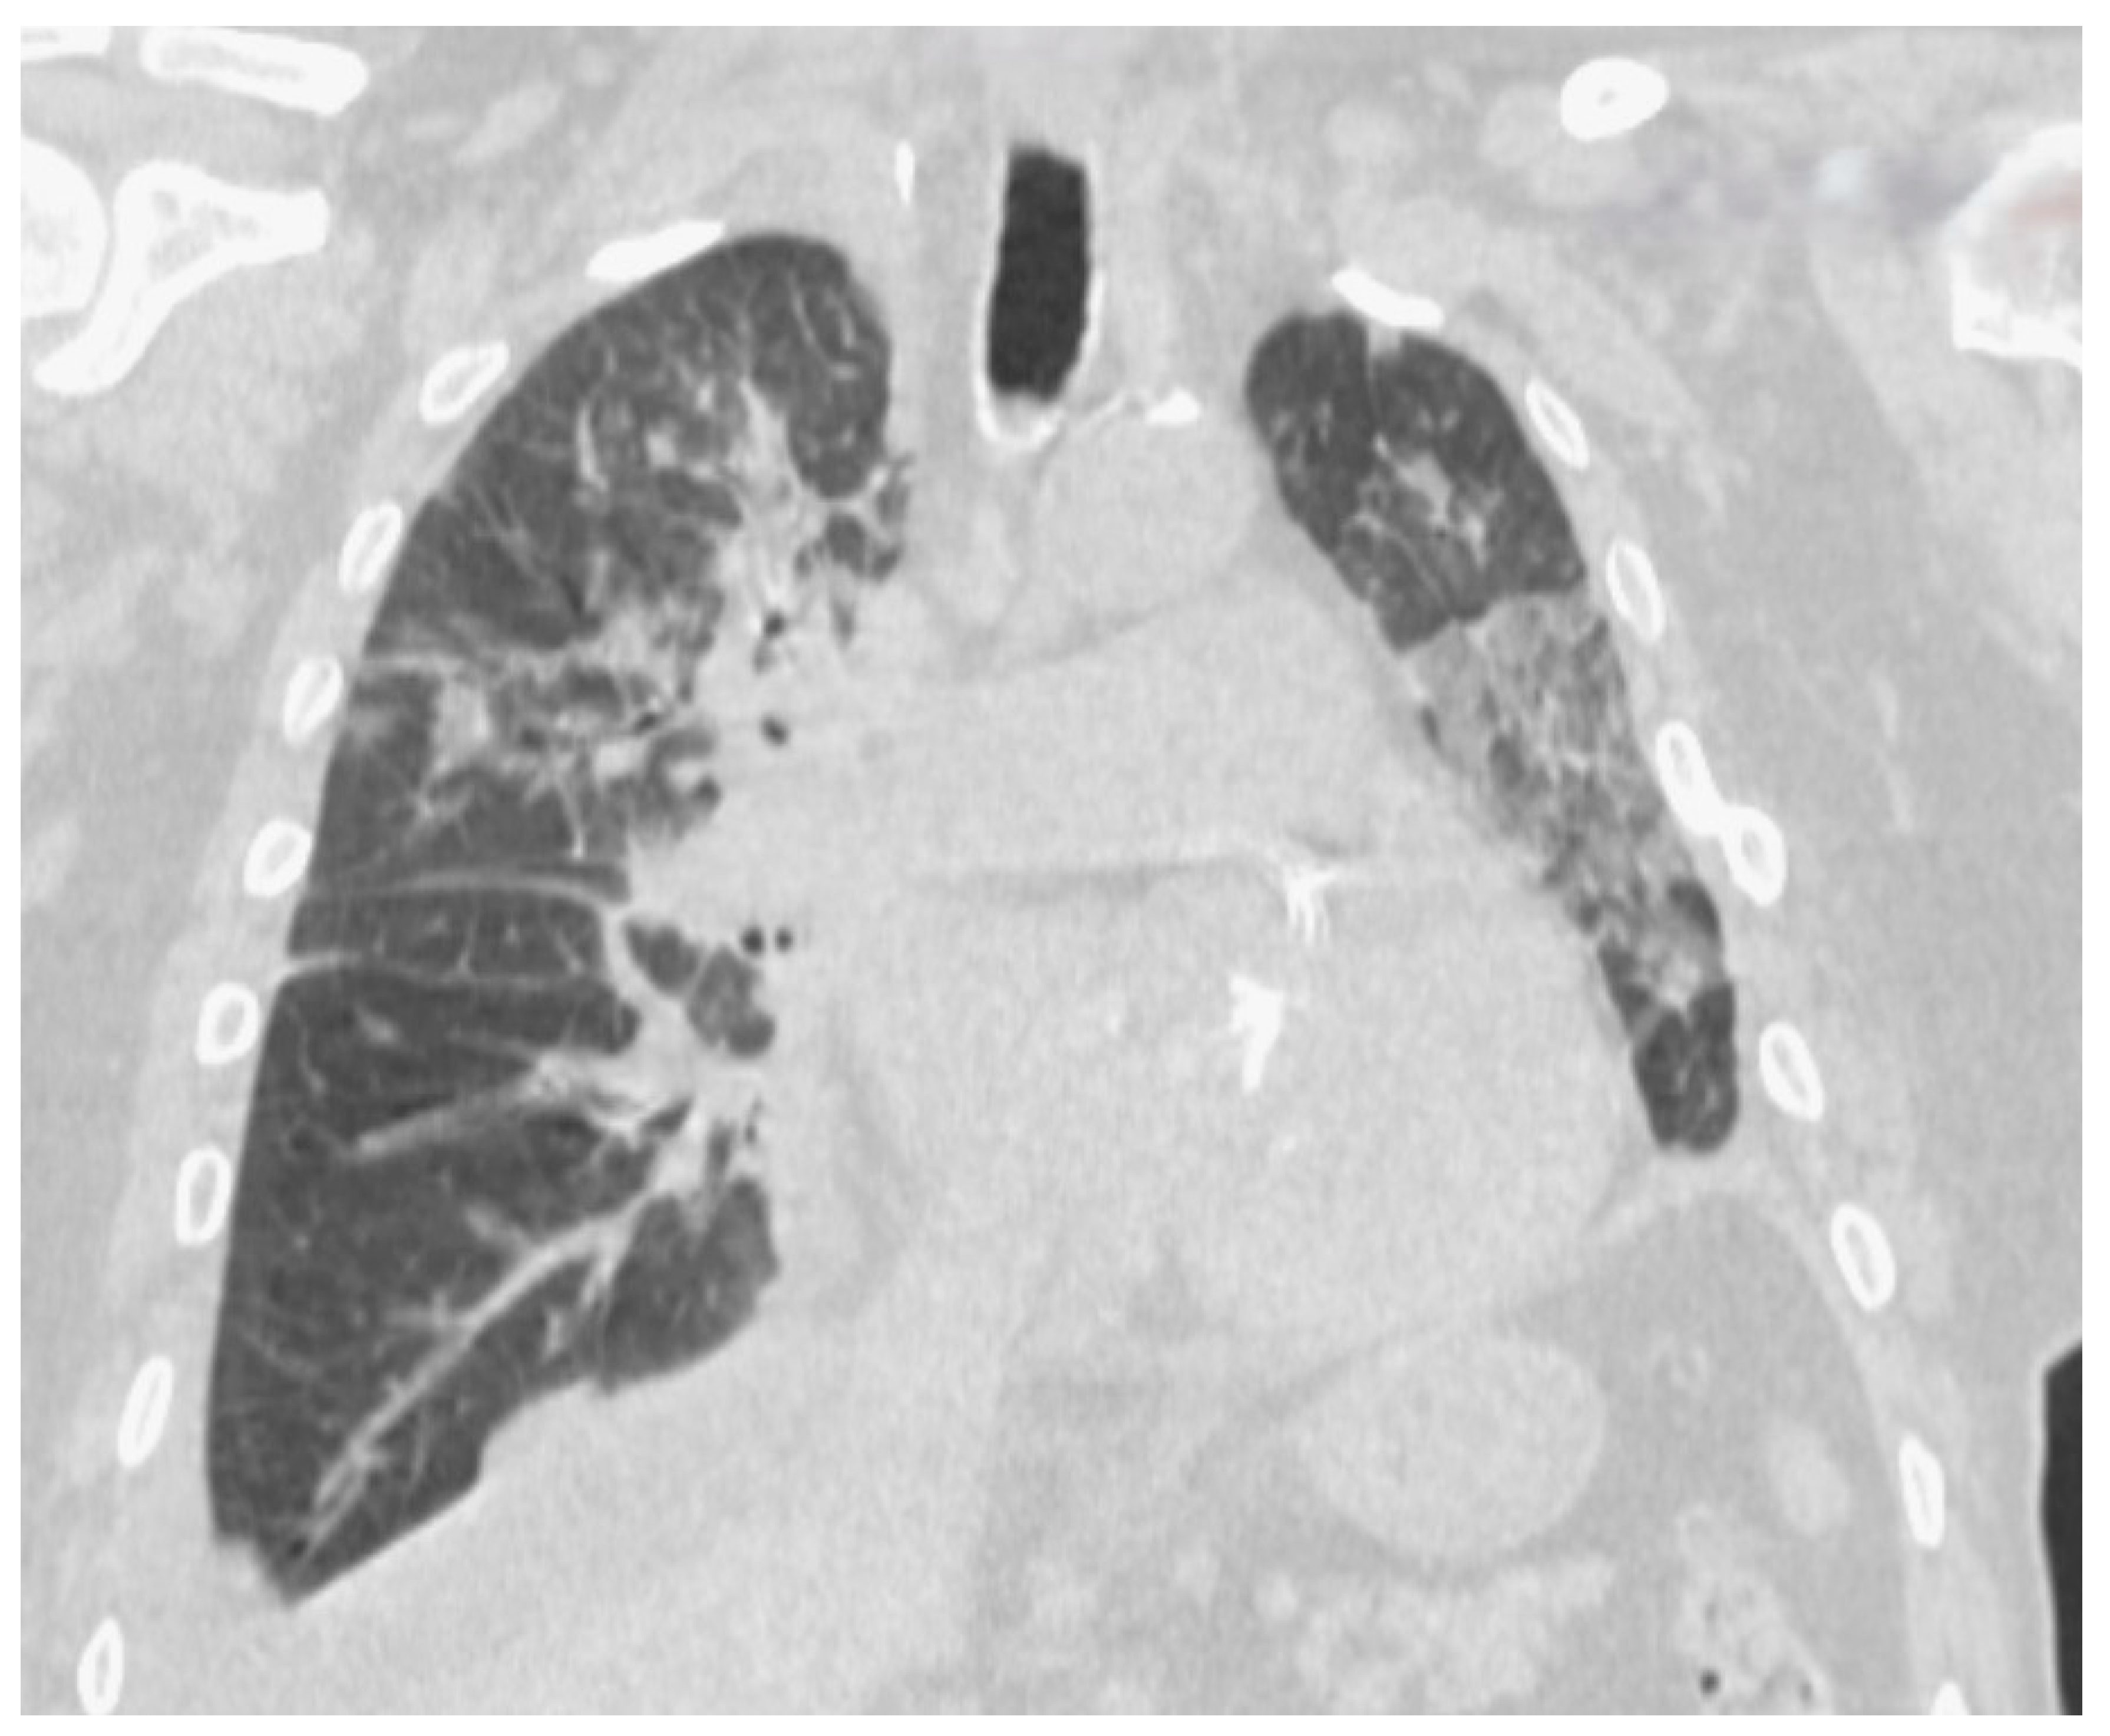

3.3. AMI-COVID-19 Imaging Studies

3.4. Two-Case Presentation Series